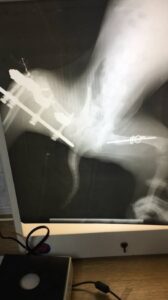

Operationsfotos

Von unserem Patienten (siehe vorletzten Bericht) haben wir hier einige Fotos der erfolgten, erfolgreichen Operation: